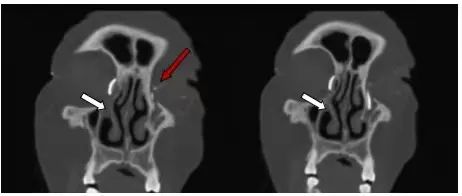

冠状位重建示:左侧泪道狭窄(红色箭头);右侧鼻泪管阻塞(白色箭头),右侧泪囊尚可见造影剂。